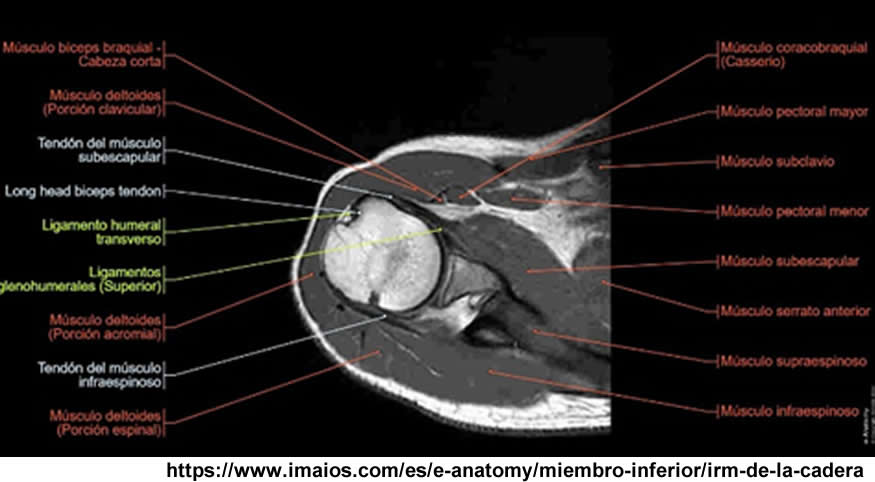

Se realiza estudio de resonancia magnética con un equipo de 1.5 tesla, se aplica protocolo de sedación, se utiliza bobina fase arrays, y se procede a adquirir un PSP, en tres planos, secuencias Se, ponderadas a T1 y T2, se administra medio de contraste por vía I.V.

La diáfisis femoral proximal se ve totalmente destruida, a nivel del hombro izquierdo la cabeza del humero no se observa.